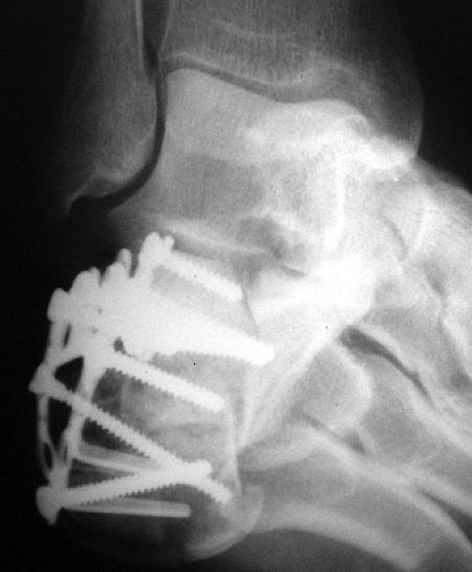

Окончательная фиксация спицами, пяточными пластинами (5) , в последнее время стали применять крючковидные пластины (ДЕОСТ) (6,6a).